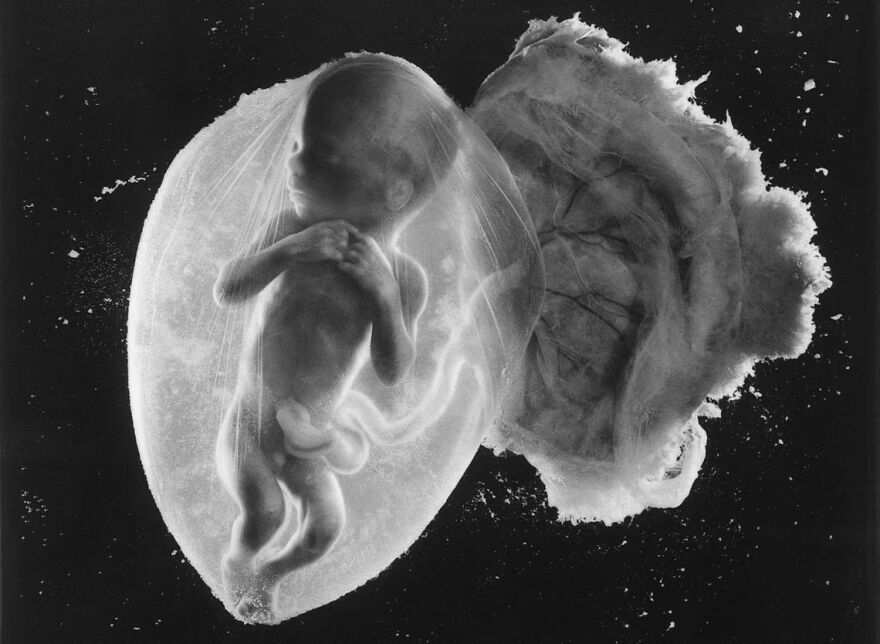

Fetus, 8 weeks (10), approximately 4 cm (1.6 inches)

From the book "A Child is Born", 1965